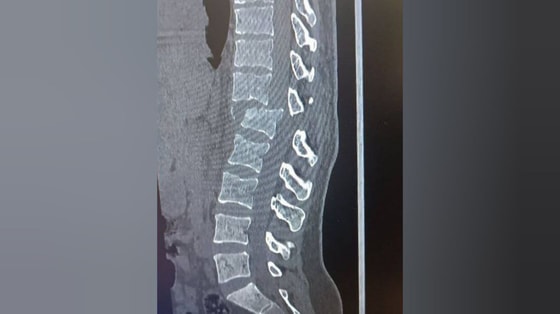

14 августа утром Ш. за рулем Damas наехал на З., когда она вышла из дома и шла по краю дороги. Из-за наезда З. получила тяжелые травмы: перелом позвоночника, повреждение нервных окончаний и паралич нижней части тела, — отметили в проекте.